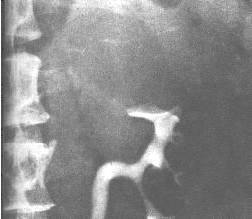

4、X線檢查:在腹平片中常可見到腎影中有一部分膨大或其上有一包塊壓迫。囊腫的重量或位置可引起腎臟扭轉導致腎軸異常。有時在腫塊邊緣可見到條紋狀鈣化影。排泄性尿路造影可確診。在靜脈推注造影劑後1~2分鐘攝片中,可見腎實質血管密度增高,而囊腫占據的那部分空間則不會,因為其中沒有血管。尿路造影連續攝片顯示有包塊存在。囊腫周圍的一個或數個腎盞或腎盂常因凹陷或彎曲,而變得增寬、變平甚至管腔消失。斜位或側位片也是有助於診斷。當包塊占據了腎下極,輸尿管上段便會向脊柱移位。腎臟本身也會發生鏇轉。通過可透射線的囊液或以看到腰大肌。當常規尿路造影不能有效區分不透光的腎實質時,腎斷層X線攝影術可增大有血管的腎實質與囊腫的對比度。偶見腎實質腫瘤亦有相對無血管,從而易與囊腫相混淆。少數情況下,囊腫壁也可發生腫瘤,因此有必要作更進一步的鑑別診斷檢查。